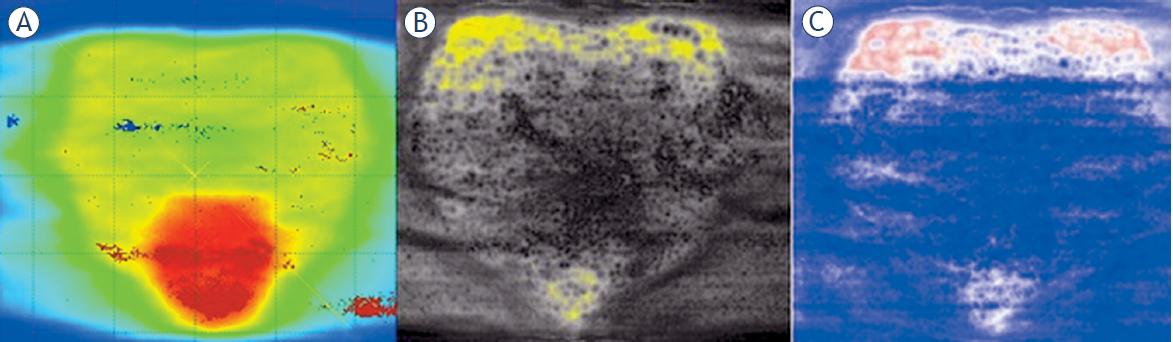

The results of the gamma analysis from the type of films and the three software products can be found in Table 1. The parameters of the gamma analysis were: 3%, 3 mm, and 2%, 2 mm, the negligible threshold dose was 10%, and the normalization of gamma analysis was performed on global dose maximum. A sample result - the evaluation of the RA-SIB plan with three software programs can be found in Figure 3.

Evaluation of the simultaneous integrated boost (SIB) plan with PTW Mephysto (A), FilmQAPro (B) and radiohromic.com(C).